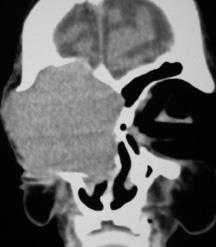

По данным рентгенографии и КТ была выявлена распространенная опухоль орбиты с распространением на мягкие ткани параорбитальной зоны, ограниченным разрушением нижней костной стенки передней черепной ямки без интракраниального распространения (рис. 2).

Левосторонний микрофтальм у маленького ребенка. КТ, аксиальная проекция: пациент представленный на рисунке выше; определяется глазное яблоко маленьких размеров и крупная ретробульбарная киста. Правосторонний микрофтальм у мужчины 57 лет. Аномалия наблюдается с рождения. КТ, аксиальная проекция: пациент, представленный на рисунке выше; позади микрофтальмического глаза определяется кистозное образование. Типичный внешний вид пациента с крупной колобоматозной кистой в нижней части глазницы, смещением микрофтальмического глазного яблока верх и выпячиванием нижнего века. Макропрепарат микрофтальмического глаза (справа) и колобоматозной кисты (слева).

б) Диагностика. Диагностике помогают ультразвуковое исследование и компьютерная томография. При ультразвуковом В-сканировании определяется микрофтальмический глаз, колобома и прилегающее к колобоме кистозное образование (6). При КТ и МРТопределяется округлое или неправильной формы кистозное образование, прилегающее к микрофтальмическому глазу (7).